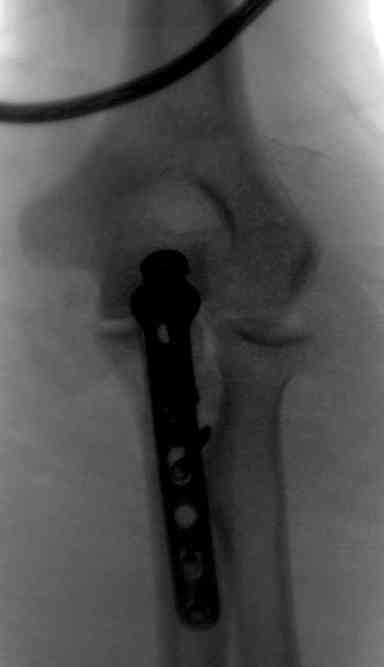

При самом большом к Вам уважении, Сергей Анатольевич, не соглашусь. У меня, после того, как добавили "прямой" снимок, сомнений не осталось. Венечный сломан наверняка. Но чтобы судить, насколько это критично для стабильности, нужно иметь строго боковую проекцию. И при этом помнить, что на него крепятся медиальные связки.

Прикрепляю снимок, где обведен фрагмент, несущий на себе венечный отросток (весь он смещён с этим фрагментом или частично - без качественной боковой проекции судить сложно), и отдельно на снимке обведено "ложе", от которого он сместился.

Почему я в данном случае против Вебера (хотя обычно горячий сторонник)? Да потому, что спицам нередко не хватает жёсткости, чтобы удержать предплечье от волярного подвывиха. При таком оскольчатом переломе спицы порой просто "прогибаются" за счёт одного только натяжения проволочной петли и головка луча может уйти в волярный подвывих (может, конечно, и не уйти). Но я бы предпочёл фиксировать всё к жёсткой пластине (включая фрагмент с венечным отростком) и, по возможности, исключить послеоперационную внешнюю иммобилизацию. Накладывать на такой локоть после операции гипс -- означает обрекать его на тяжёлую контрактуру.

Головка луча, кстати, на мой взгляд цела.